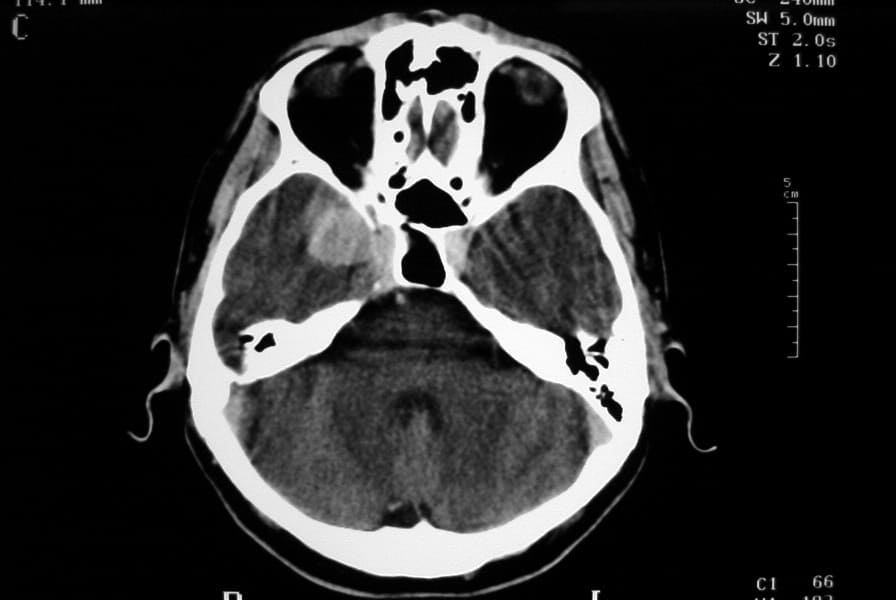

Signos y exámenes

El examen muestra, a menudo, signos neurológicos generales o focales que son específicos del sitio del tumor. Algunos tumores no muestran síntomas hasta que ya son bastante grandes y causan rápido deterioro neurológico, mientras que otros se caracterizan por los síntomas progresivos lentos. La mayoría de los tumores muestra signos típicos de masas que ocupan espacio (lesión ocupante de espacio: LOE), los cuales causan aumento de la presión intracraneal y compresión del tejido cerebral.

El diagnóstico se puede confirmar y el tumor localizar mediante:

• TAC cerebral

• RM cerebral